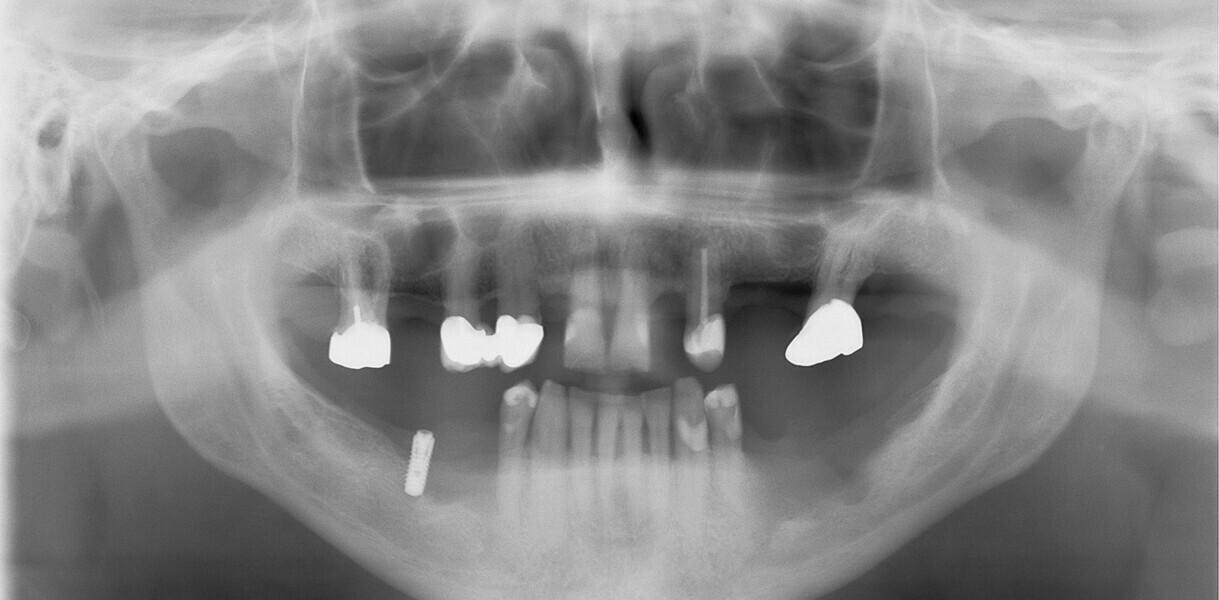

Fig. 14: Dental panoramic tomogram of initial situation.